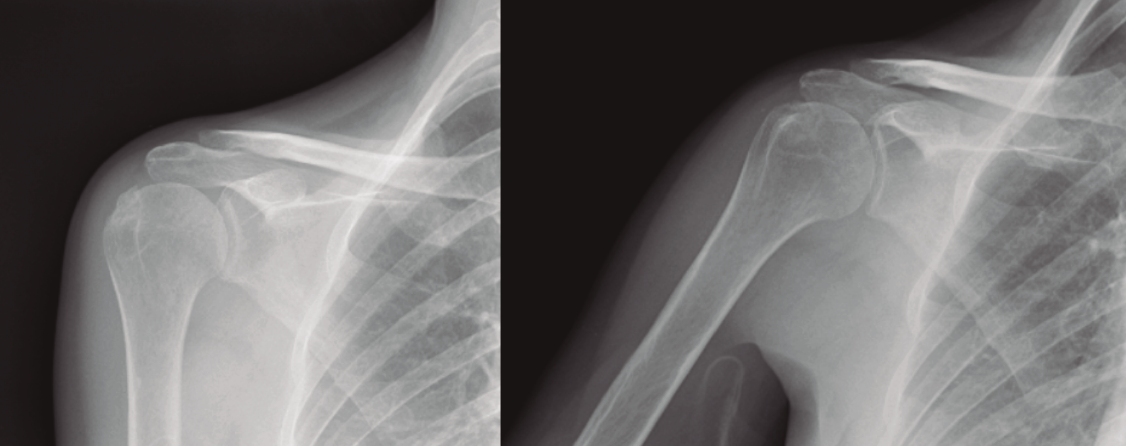

Protocolo rehabilitador en fracturas de húmero proximal no quirúrgicas (Figura 1)

Figura 1. Radiografía de una fractura de húmero tributaria de tratamiento conservador.